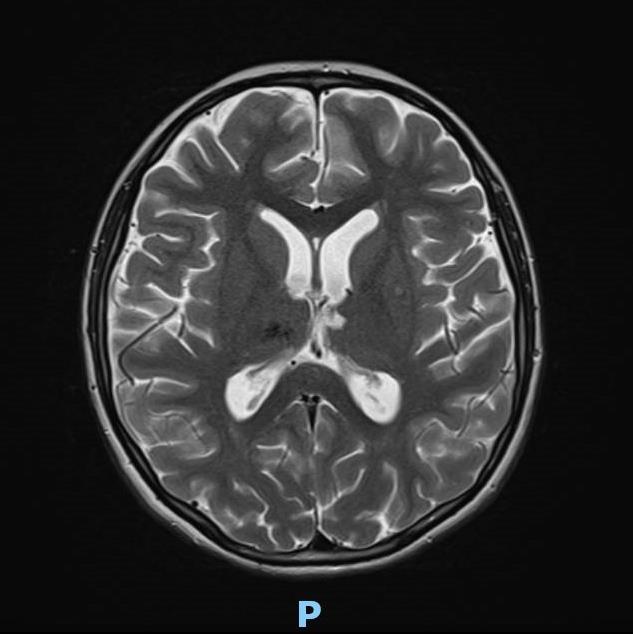

On the MRI, the diffuse axonal damage in this child is evident in the brainstem, isthmus, and splenium of the corpus callosum, the thalami, the subcortical and deep white matter in the frontoparietal regions of both hemispheres, and in the white matter of the right cerebellar hemisphere.